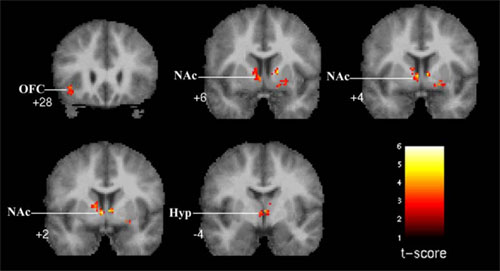

Vídeo-instalación: “La respuesta cerebral a la música: un estudio con RMf”

Jesús Pujol, Héctor Ortiz y Carles Soriano-Mas Instituto de Alta Tecnología-PRBB, CRC Corporación Sanitaria, Hospital del Mar.

** Brain excited by music. Image by Daniel Levitin, from Wired story on his work